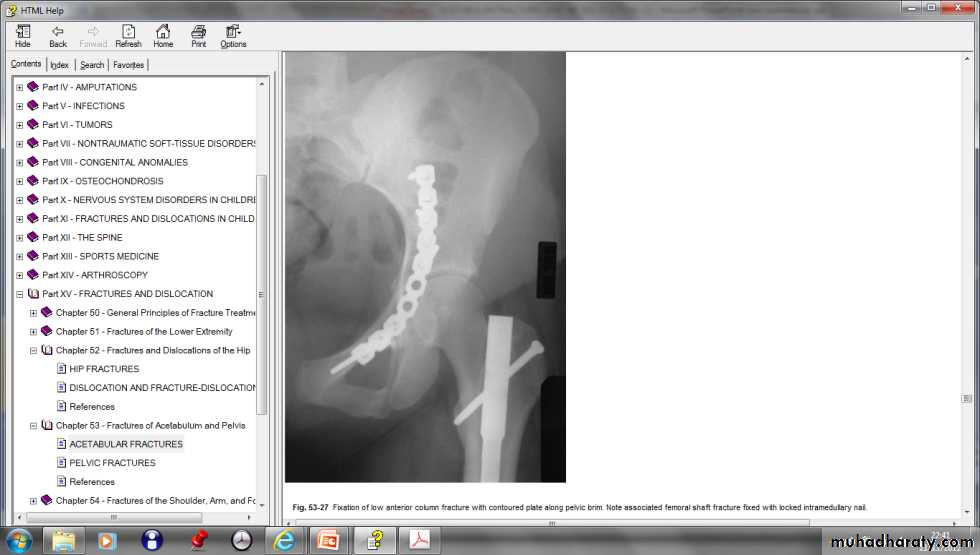

Fracture acetabulum

Fractures of the acetabulum occur when the head of the femur is driven into the pelvis.This is caused either by a blow on the side (as in a fall from a height or road traffic accident ) or by a blow on the front of the knee, usually in a dashboard injury when the femur also may be fractured.

There is usually history of a severe injury; associated fractures are not uncommon and may divert the attention from the more urgent pelvic injuries. Whenever a fractured femur, a severe knee injury or a fractured calcaneum is diagnosed, the hips also should be x-rayed. The patient may be severely shocked. There may be bruising around the hip and the limb may lie in internal rotation (if the hip is dislocated).Neurological examination is important, testing the function of the sciatic, femoral and obturator . Several X-ray views of the hip are needed to visualize the fracture accurately. CT scans are particularly helpful if surgical reconstruction is planned.